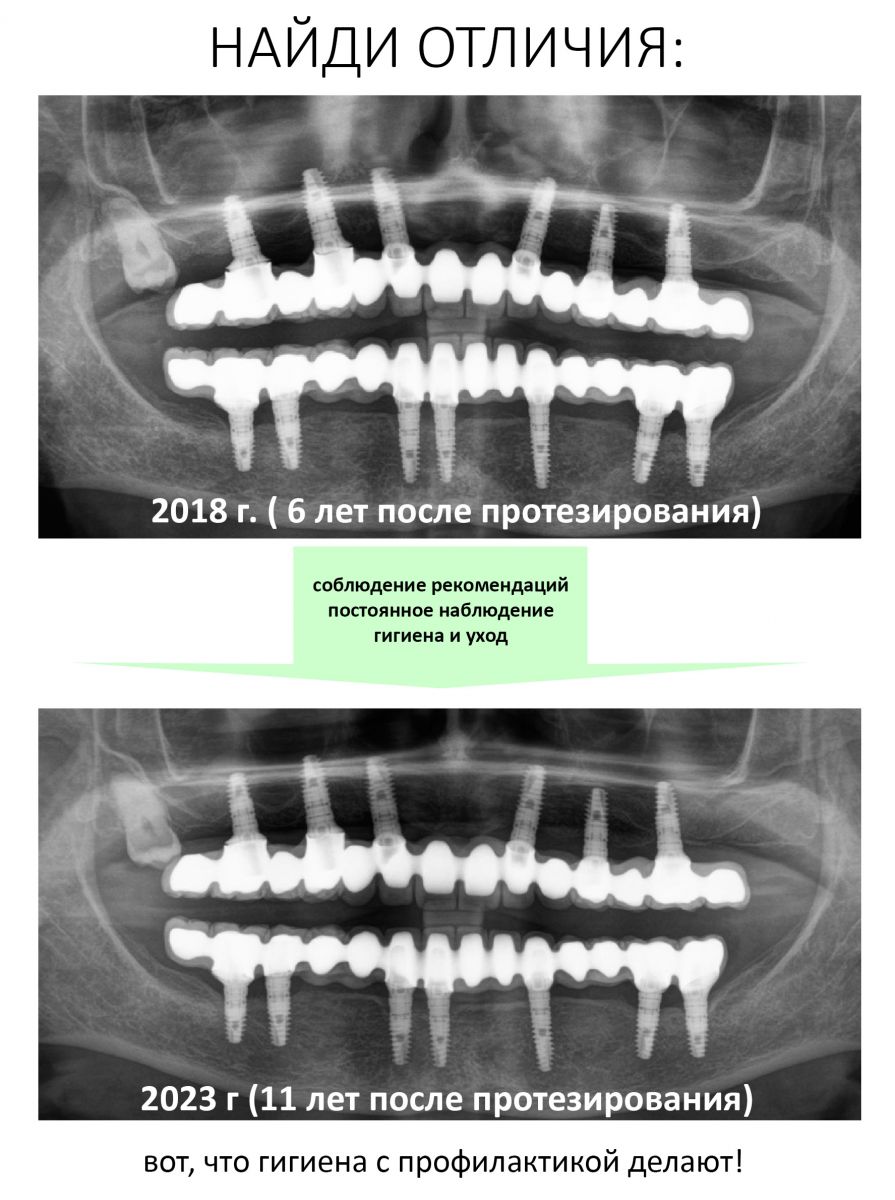

К счастью Елена (так зовут пациентку) оказалась очень ответственной: каждый год она приходит в нашу уютную Клинику ИН, мы делаем контрольные снимки, проводим профессиональную гигиену полости рта, которую она в течение года поддерживает гигиеной индивидуальной. Она помнит, чего стоило проведенное лечение как по финансам, так и с точки зрения нагрузки на её хрупкий женский организм, потому никогда не пропускает профилактические осмотры.

Собственно, я не зря выбрал в качестве примера столь нетривиальный и даже спорный клинический случай. Он наглядно демонстрирует, что выполнение пациентом рекомендаций по уходу и профилактическим осмотрам обеспечивают длительный срок службы имплантатов даже тогда, когда протетическая конструкция этого, вроде как, не предполагает. Иными словами, «несмотря на все усилия врачей, пациент остался жив» — и продолжает жить полной жизнью, посещая уютную Клинику ИН раз всего раз в год.

Чтобы этого не произошло, достаточно выделить всего 1/8760 часть года и приехать в клинику на профилактический осмотр, во время которого твой стоматолог осмотрит область имплантации, сделает контрольные снимки и даст рекомендации по уходу за полостью рта. Разумеется, если он заметит какие-то проблемы в области установленных имплантатов и зубных протезов, то примет необходимые меры по их устранению. Таким образом, он сможет вмешаться в воспалительный процесс тогда, когда он еще не привел к катастрофе. А после — даст рекомендации по уходу.

Чем раньше обнаружена проблема — тем меньше усилий потребуется для её устранения и тем лучше будет результат. И наоборот.

Гигиена полости рта, в т. ч. профессиональная — наше всё. Последнюю можно сочетать с профилактическим осмотром, это не только экономит время, но и деньги (спойлер: для ответственных и добросовестных пациентов есть специальные условия на проф. гигиену). Кроме того, мы позаботились о том, чтобы не томить вас ожиданием: в уютной КЛИНИКЕ ИН работают два гигиениста с двумя аппаратами EMS Prophylaxis Master. То есть, попасть к доктору и почистить зубы можно в любой день.